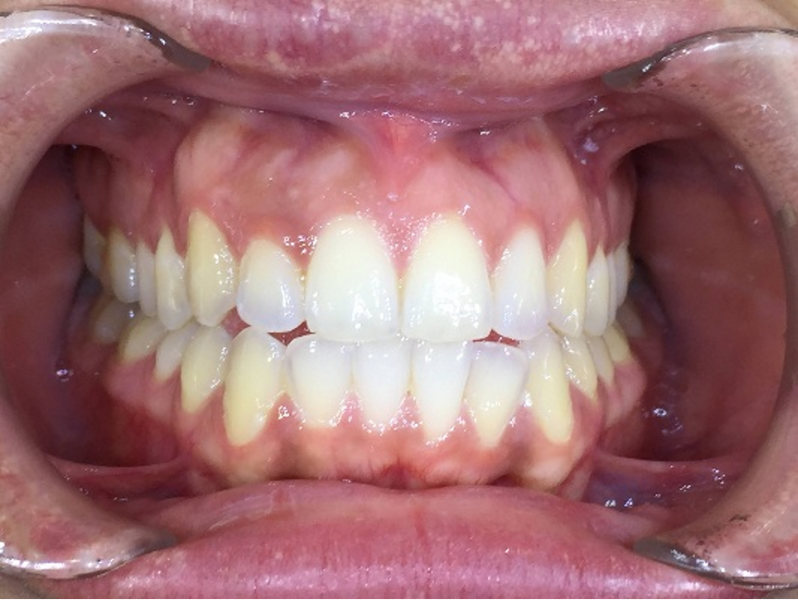

After six months of weekly changeover of aligners (25 out of 33 aligners in the maxillary arch and 25 out of 25 aligners in the mandibular arch and no refinement) and achieving adequate intrusion of the six maxillary anterior teeth, the pre-restorative segment of the treatment was complete (Figs. 5 & 6). The next phase was a digitally planned soft-tissue recontouring of the labial tissue of the six maxillary anterior teeth. For this purpose, a digital surgical guide was made by our laboratory at AORTA using our PRO 4K printer (Asiga; Figs. 7–10). This was followed by in-chair tooth whitening and then composite augmentation of the incisal edges of teeth #13–23 (Figs. 11 & 12). The patient was then placed into retention with Zendura FLX thermoplastic retainers (Bay Materials) based on resin 3D-printed models produced by our PRO 4K printer, providing accuracy and superior fit as observed by the patient. The retainers and models were all made by our dental laboratory at AORTA.

Fig. 3: Close-up view of the patient’s smile.